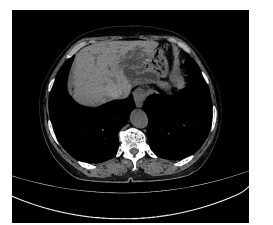

Primary fibrosarcoma of the liver misdiagnosed as hepatic abscess: A case report

Liuyang ZHU, Jiancun HOU, Long YANG, Wen TONG, Yamin ZHANG

2021, 37(7): 1665-1667. DOI: 10.3969/j.issn.1001-5256.2021.07.037

Abstract(896) HTML (266) PDF (3350KB)(81)